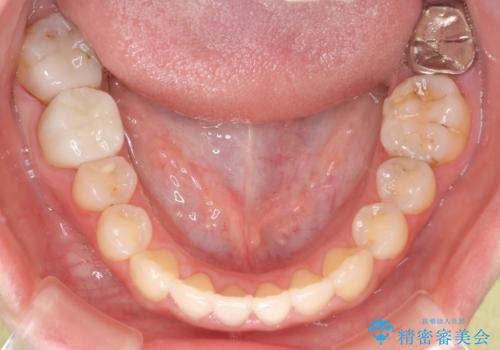

八重歯をインビザラインで非抜歯矯正

- 八重歯を主訴に来院されました。

インビザラインにて奥歯を後方に移動して八重歯が入るスペースを確保してく矯正する計画としました。

八重歯と前歯のガタガタがなくなり、歯並びがきれいになったのと、かみ合わせも改善することができました。